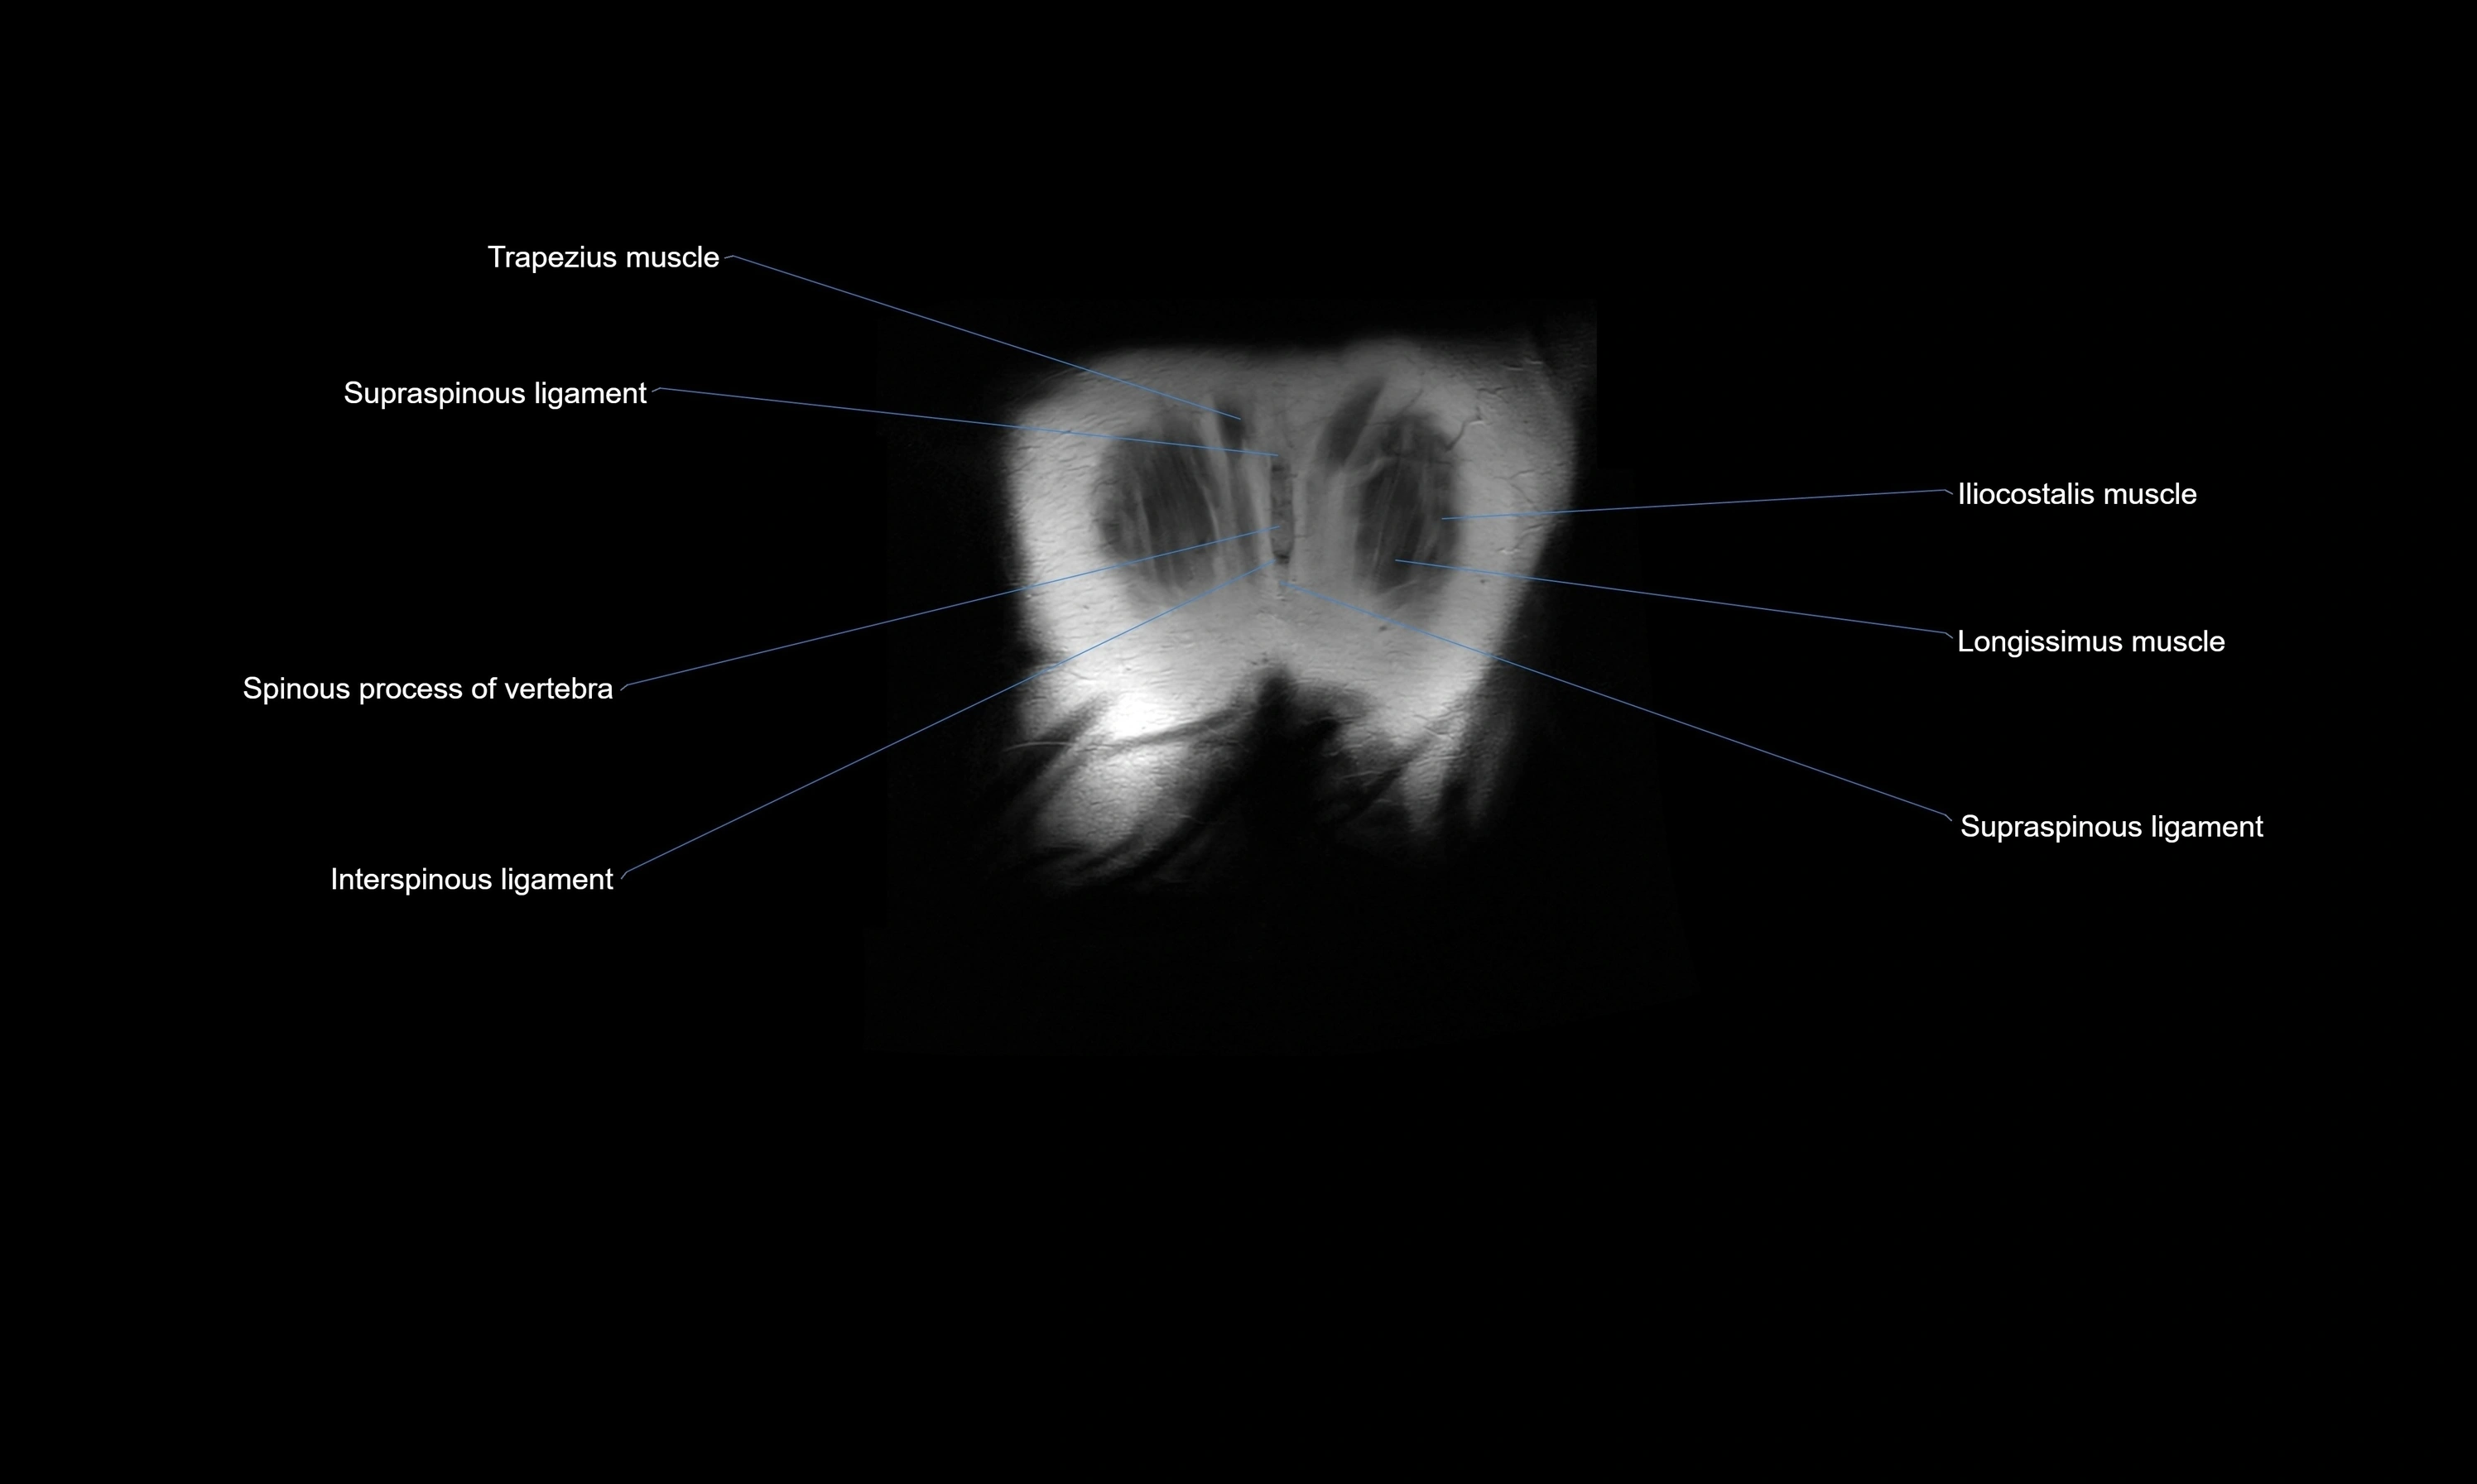

- Interspinous ligament

- Longissimus thoracis muscle

- Spinous process of vertebra

- Supraspinous ligament